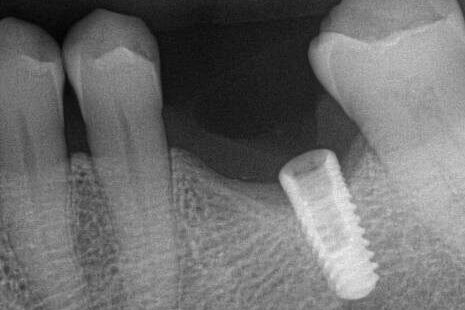

This next case is very similar to the above Type I case, with the exception that the lead screw thread fragment was about a half thread below the lead implant thread. This is a DIO 3.0 implant that had an initial tight contact issue and when returning to the office, the abutment screw was fractured. There were no prior recovery efforts. The difference in these two cases is that a Type III case can be more difficult to rotate up, because the fractured lead thread can be sharp and as it is leading in the counterclockwise rotation, it can catch into an implant thread. Without adequate visualization, the case can be easily mistaken for a non-mobile Type IV case. Often upward rotation progress is slow until the lead fragment thread emerges from the implant threads, converting the case into a Type I case. This situation is diagnosed when the fragment can rotate freely down (clockwise), but with difficulty up (counterclockwise). This issue is difficult to appreciate with only loop magnification.